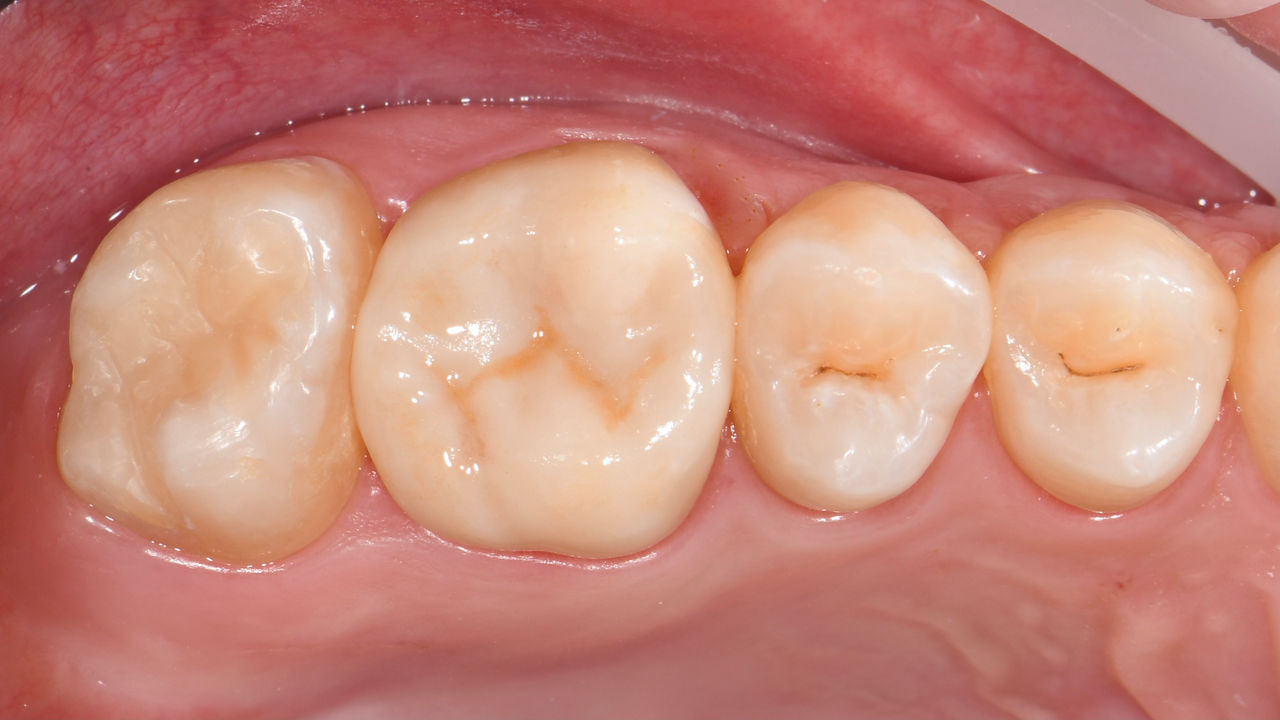

Quadrant rehabilitation

Two CEREC Tessera crowns and two inlays

Within a single visit of four hours the restoration of two crowns and two inlays, which were 15 years old, was carried out. The patient was very pleased with the very good aesthetic result.

Before: Insufficient fillings in the second quadrant. The restorations were about 15 years old.

After: Chairside-fabricated crowns made from CEREC Tessera (teeth 26/27). Inlays for teeth 24 and 25 made of composite blocks.

Dr. Andreas Bindl

Zurich, Switzerland